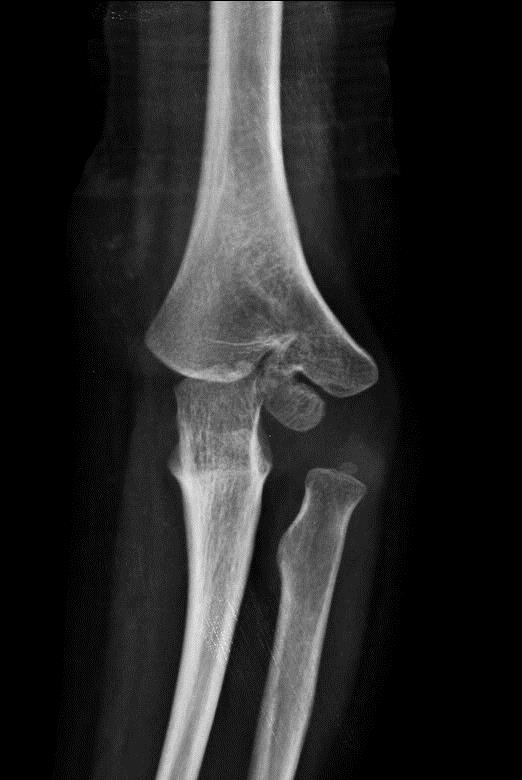

A sevenyearold boy with a PFPSpositive displaced extension type

A sevenyearold boy with a PFPSpositive displaced extension type Extension Type Supracondylar Fracture Orthobullets The majority of nerve injuries associated with pediatric extension schf recover within 6 months without acute nerve decompression. The gartland classification of supracondylar fractures of the humerus is based on the degree and direction of displacement, and the presence of intact cortex. Generalized swelling about the elbow could be present;. Learn about the anatomy, classification, diagnosis and treatment of distal. Extension Type Supracondylar Fracture Orthobullets.